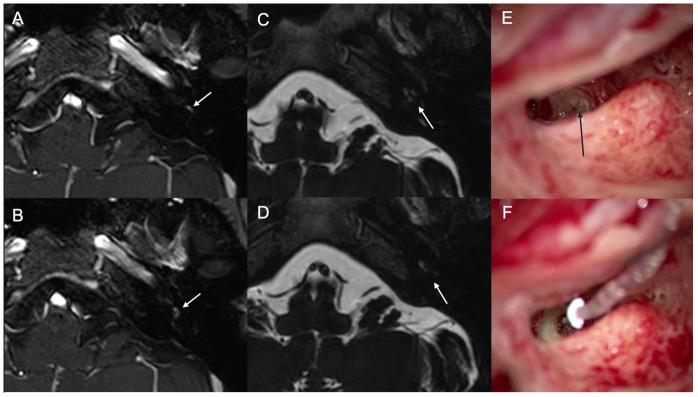

: Simultaneous removal and cochlear implantation (CI) have been reported in intralabyrinthine and intracochlear schwannoma. A wide range of postoperative hearing outcomes have been reported after CI in these cases. This study evaluated the outcomes of performing a simultaneous resection of Schwannoma in cochlea and cochlear implantation (CI), aiming to assess the effectiveness of this combined surgical approach for hearing rehabilitation with CI. : This retrospective case series was conducted at a tertiary care center. The study included four consecutive patients with profound sensorineural hearing loss due to a mass inside the cochlea. These patients underwent simultaneous single-sided CI and tumor resection performed by the same surgeon. Preoperative and postoperative audiological assessments were conducted to evaluate the patients' hearing outcomes before and after the surgical intervention. : Simultaneous CI with tumor resection was successful in all cases. Two of the four patients had a unilateral tumor, while the other two had a bilateral tumor with the involvement of the internal auditory canal and cerebellopontine angle (neurofibromatosis type 2 (NF2)). In two cases of unilateral tumor, aided free-field pure tone average (PTA) was 26 dB, and 46 dB hearing level (HL), and word recognition score (WRS) at 65 dB was 40% and 68%, respectively, 3 months after surgery. In two cases of tumor with NF2, aided free-field PTA was 36 dB and 60 dB HL, and both cases showed 0% WRS at 65 dB 3 months after surgery. : Simultaneous schwannoma excision and CI in patients with Schwannoma inside cochlea are surgically practical and safe. Postoperatively, there was a notable improvement in hearing in cases of sporadic schwannoma, regardless of the type of CI used. However, there was 0% WRS in the two NF2 patients with a mass in the internal auditory canal.

: 据报道,在迷路内和耳蜗内神经鞘瘤中可同时进行肿瘤切除和人工耳蜗植入(CI)。这些病例中,CI术后的听力结果范围广泛。本研究评估了同时切除耳蜗神经鞘瘤和人工耳蜗植入(CI)的结果,旨在评估这种联合手术方法对CI听力康复的有效性。: 本回顾性病例系列研究在一家三级医疗中心进行。该研究纳入了4例因耳蜗内肿物导致重度感音神经性听力损失的连续患者。这些患者由同一位外科医生同时进行了单侧CI和肿瘤切除。术前和术后进行了听力学评估,以评估手术干预前后患者的听力结果。: 所有病例中同时进行CI和肿瘤切除均成功。4例患者中有2例为单侧肿瘤,另外2例为双侧肿瘤,累及内耳道和桥小脑角(2型神经纤维瘤病(NF2))。在2例单侧肿瘤病例中,术后3个月时,助听自由声场纯音平均听阈(PTA)分别为26 dB和46 dB听力级(HL),65 dB时的言语识别得分(WRS)分别为40%和68%。在2例NF2肿瘤病例中,助听自由声场PTA分别为36 dB和60 dB HL,术后3个月时,2例患者在65 dB时的WRS均为0%。: 对于耳蜗内有神经鞘瘤的患者,同时切除神经鞘瘤和CI在手术上是可行且安全的。术后,散发性神经鞘瘤病例的听力有显著改善,无论使用何种类型的CI。然而,2例内耳道有肿物的NF2患者的WRS为0%。